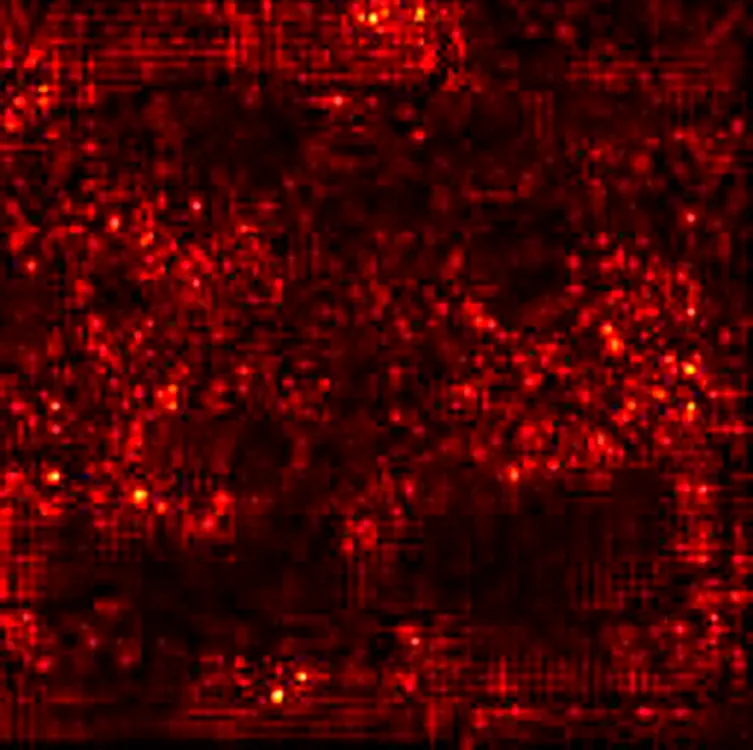

To further enhance interpretability, we selected one representative test image from each class—Normal, PCO, and Dominant Follicle—and analyzed the predicted class probabilities output by each model. Alongside each sample image, we also provide its corresponding Grad-CAM saliency map based on the best-performing model (ResNet18), which highlights the image regions that influenced the model’s decision. Table 7 presents these results, showing the image, its saliency visualization, and the predicted probabilities assigned by each model. This multimodal view helps illustrate how confidently and consistently each model responds to different ovarian conditions.

Table 7

www.frontiersin.org

Table 7. Predicted probabilities for representative images of each class across all models. Values are ordered as Normal, PCO, Dominant Follicle. Grad-CAM maps are from ResNet18.

To support model interpretability, we incorporated Grad-CAM visualizations using the best-performing architecture (ResNet18). These visual explanations highlight the specific regions of ultrasound images that influenced the model’s predictions, helping clinicians understand the basis of the classification. By providing visual cues linked to diagnostic decisions, such methods can improve trust in AI systems and facilitate their integration into clinical workflows. As shown in Table 7, combining probability outputs with saliency maps offers a more transparent view of model behavior across different ovarian conditions.